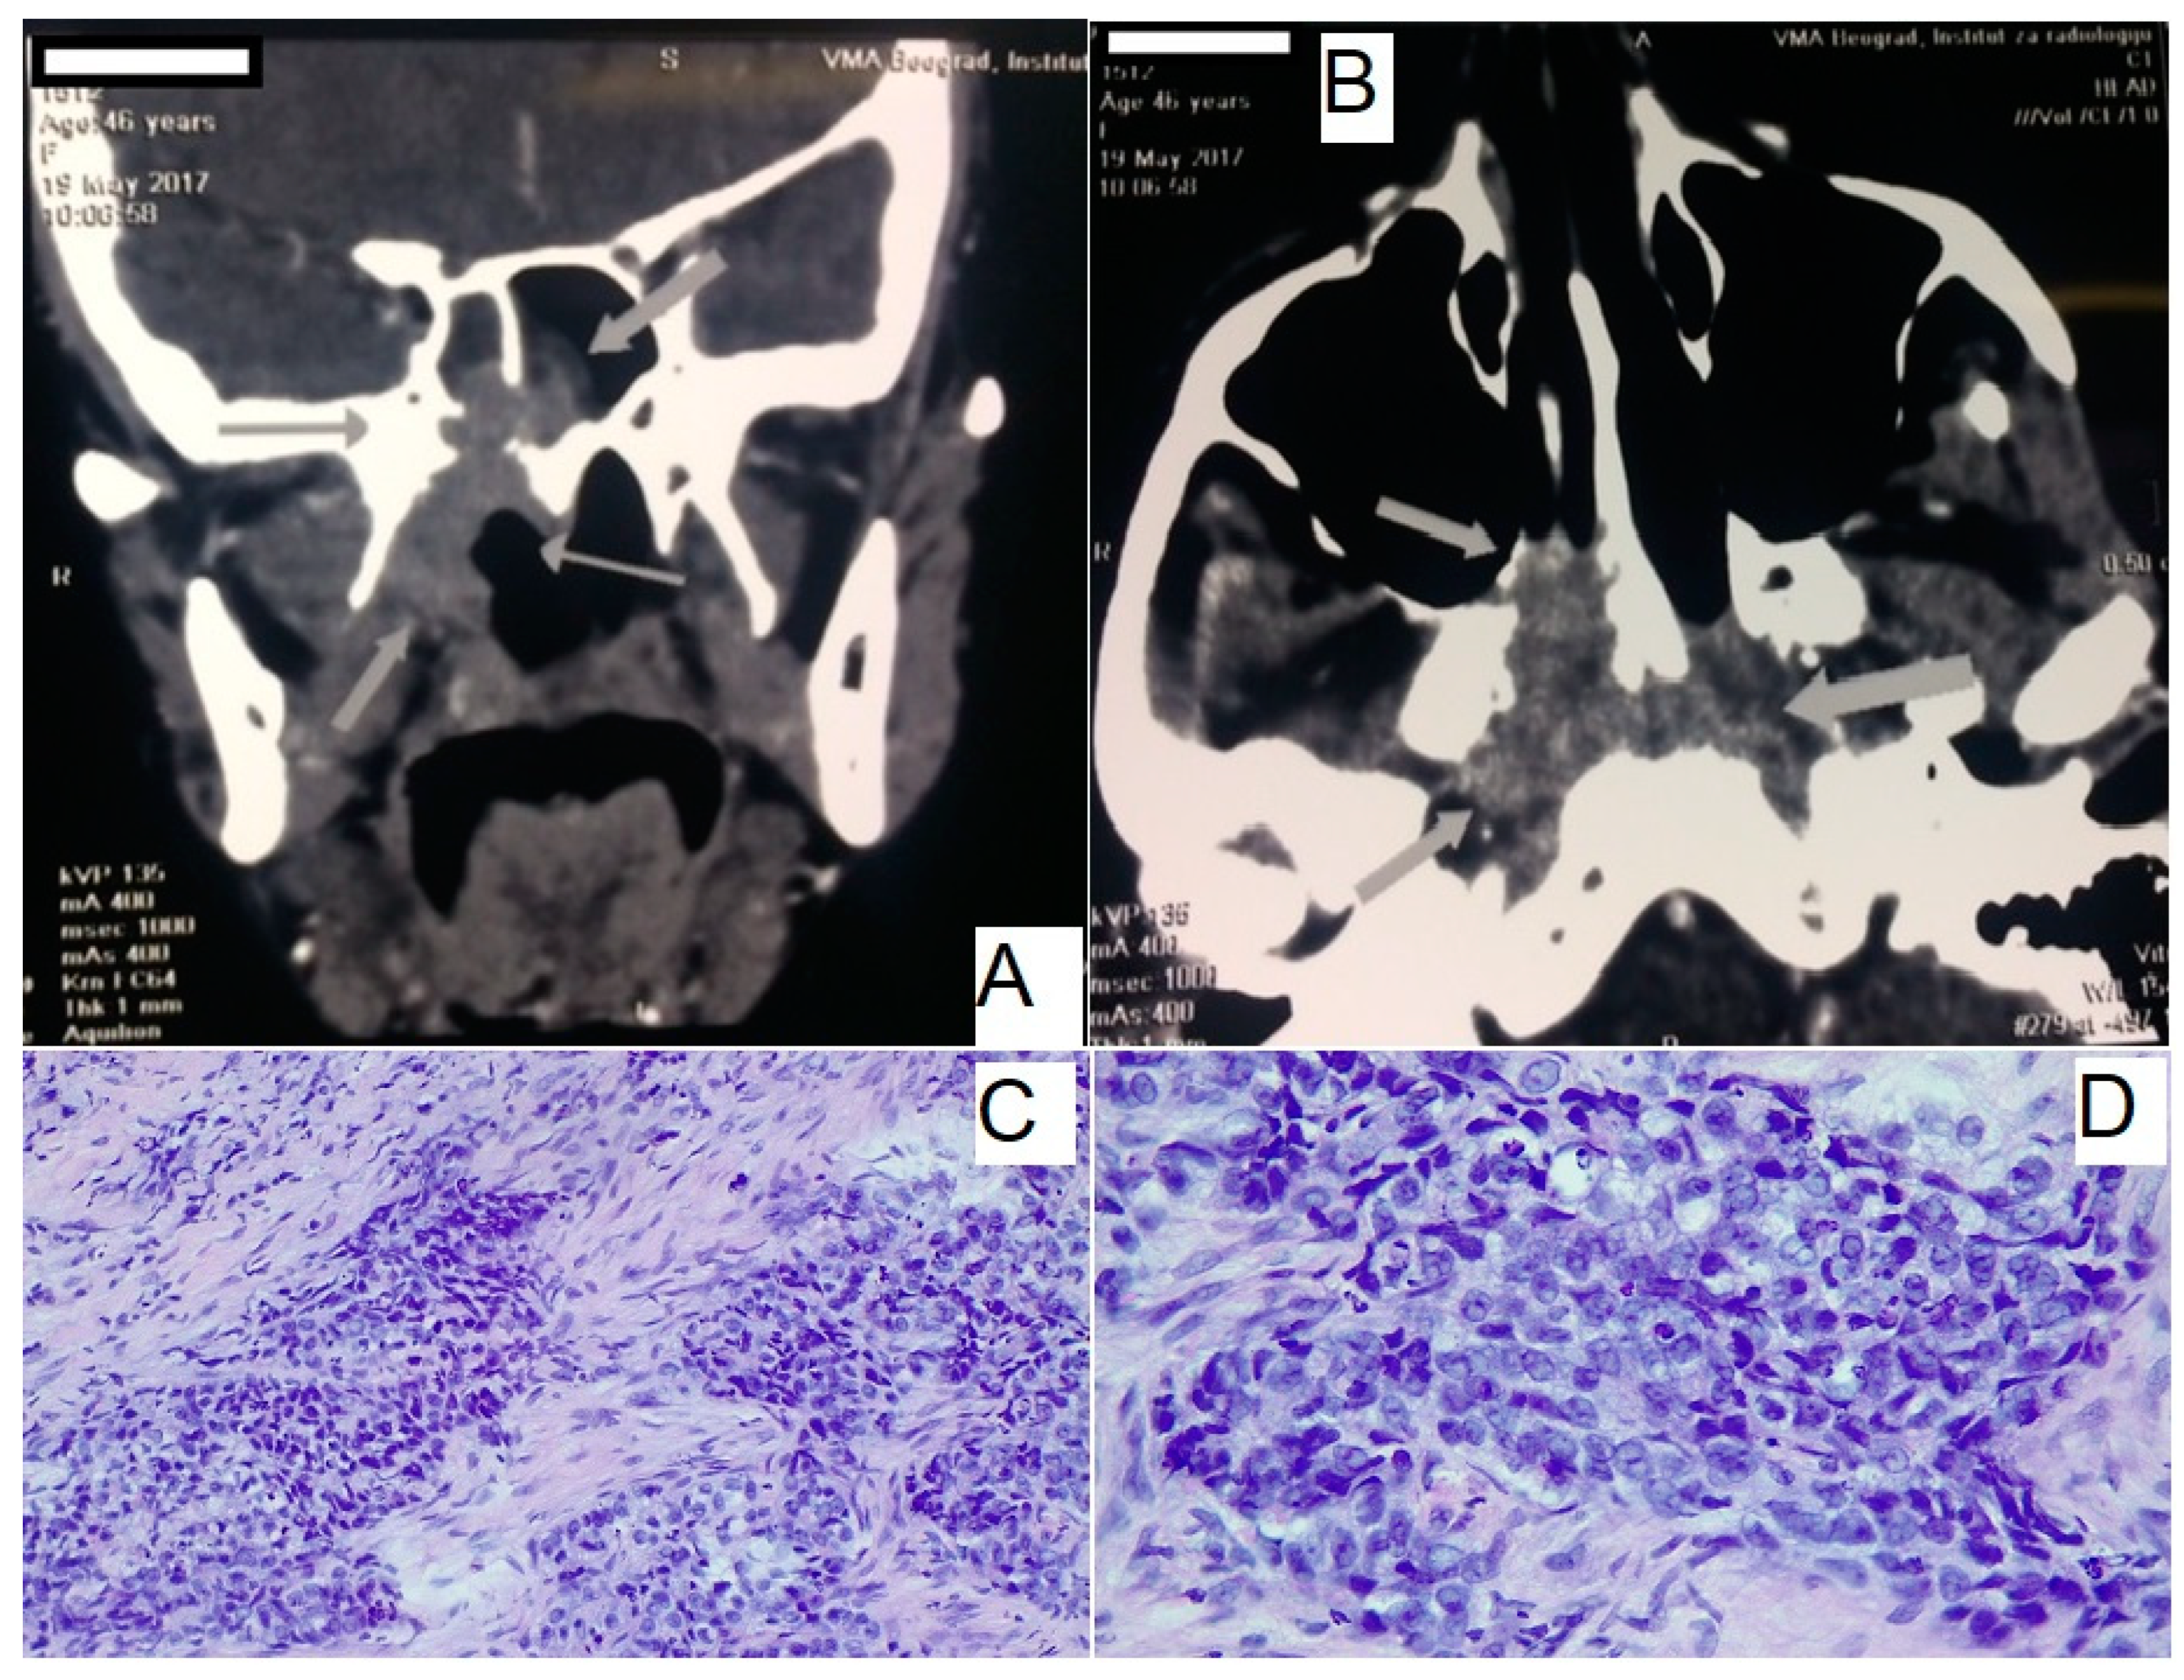

Additionally, an MSCT scan of the head and neck was performed (Figure 2A,B), which provided a detailed assessment of the tumor’s extent. The imaging revealed a mass in the epipharyngeal and nasopharyngeal regions, extending into the posterior choanae, with invasion into the sphenoid sinus and erosion of the intersphenoid septum. Posteriorly, the tumor infiltrated the prevertebral musculature without compromising the C1 vertebra.

Figure 2.

Clinical and diagnostic imaging findings. (A,B) MSCT of head and neck, showing axial and coronal views of the tumor mass. Arrows are showing tumor mass and margins of tumor. (C,D) Pathohistological analysis of the tumor biopsy, confirming the diagnosis of undifferentiated nasopharyngeal carcinoma. Hematoxylin and eosin staining reveals characteristic features, including large pleomorphic nuclei, prominent nucleoli, and a syncytial growth pattern. MSCT, Multislice computed tomography.

Further evaluation by an otolaryngology specialist through nasopharyngoscopy identified a substantial tumor mass located on the upper wall of the epipharynx. A biopsy of this lesion confirmed the diagnosis of undifferentiated NPC (Figure 2C,D).